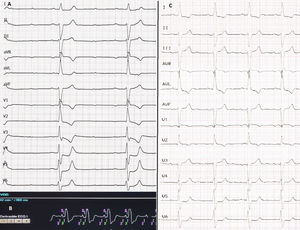

Ingresado en el hospital para implante de prótesis aórtica percutánea (fig. 1, flecha rosa) por estenosis aórtica muy severa y alto riesgo quirúrgico. Al tercer día del procedimiento, presentó bloqueo auriculoventricular completo con ritmo de escape con morfología de bloqueo de rama derecha similar al basal a 29lpm (fig. 2A).

Presentaba un alto riesgo de complicaciones vasculares con un sistema de estimulación convencional (infección del sistema de la prótesis aórtica y del catéter permanente), así como un elevado riesgo hemorrágico. Por ello se decidió implante de marcapasos sin cables AV para favorecer la sincronía auriculoventricular (fig. 1, flecha azul). El procedimiento se realizó sin complicaciones, con una detección de onda R de 8,5mV y un umbral de 0,5V a 0,24ms con una correcta sincronía AV (fig. 2B).

El electrocardiograma al alta mostró ritmo sinusal con estimulación ventricular con eje inferior y morfología de bloqueo de rama izquierda (fig. 2C). Este abordaje nos permitió minimizar el riesgo de complicaciones; es además el primer caso publicado de marcapasos sin cables AV en un paciente portador de prótesis aórtica percutánea.